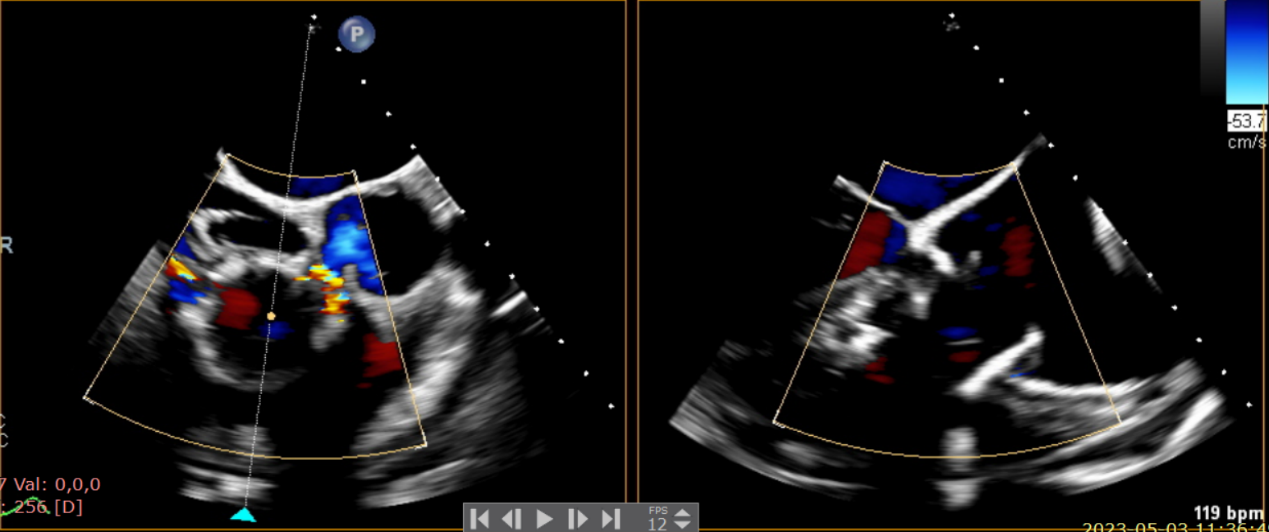

術(shù)前超聲提示大量三尖瓣反流

術(shù)中輸送器在超聲引導(dǎo)下調(diào)整位置